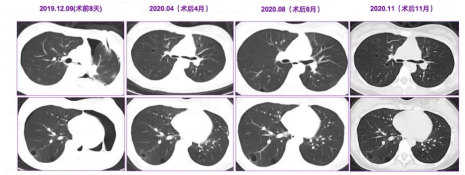

3、手术治疗与术后随访

(1)患者接受全麻下气管下段病变切除+左主支气管袖式切除+隆突成型术,术后病理结果与术前活检一致。

(2)术后1年随访:肿瘤无复发,患者运动量略低于同龄人;双肺囊性病变仍存在,部分囊腔有增大趋势,但术后未再出现肺部斑片影。